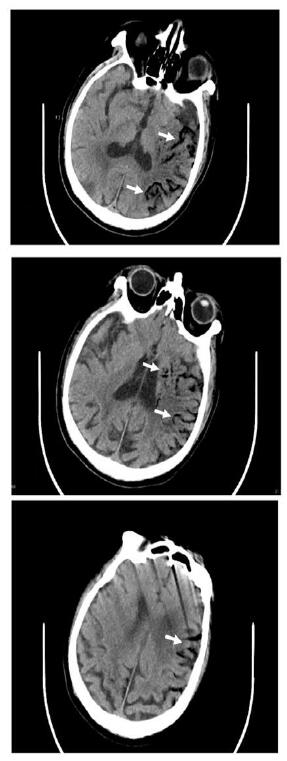

1 资料与方法患者,男,68岁;因“间断胸闷心慌1个月余,呕血伴发热1 d,意识障碍12 h”收入华中科技大学同济医学院附属同济医院。患者一个月前自觉胸闷、心慌,至当地市级医院诊断为“房颤、冠状动脉粥样硬化”,入院前34 d行房颤消融术+冠脉造影术,术后口服达比加群酯110 mg 2次/d,术后3 d再次因胸闷心慌至当地县人民医院住院治疗,给予对症治疗,症状可缓解。入院2 d前再次出现胸闷心慌等不适,入院前1日下午4时呕血约300 mL,伴寒战高热,最高可达39.5 ℃,并于入院当日中午12时出现意识障碍,言语不清,为求进一步治疗转至本院急诊科。急查头部CT示:脑萎缩,脑白质病;右侧半卵圆中心及左侧基底节区片状低密度影,考虑为缺血梗死灶;右侧小脑半球片状低密度影,考虑脑梗死、软化灶形成。后患者意识障碍较前缓解,急诊科收治入院。既往史:高血压史十余年,5年前脑梗死病史,10年前行腰椎间盘突出手术治疗,吸烟30余年,每日一包,饮酒30余年,每日250 mL,戒酒10年。入院体格检查:患者意识清醒状态,言语沟通不畅,心电监护提示:血压105/80 mmHg,脉搏87次/min,SPO2 100%,心率18次/min;双侧瞳孔等大等圆,直径2.5 mm,对光反射存在,双肺呼吸音粗, 未闻及啰音;心音可,律齐,未闻及杂音;腹软,移动性浊音阴性,肠鸣音正常。四肢无畸形,四肢活动无障碍,双下肢无水肿,生理反射存在,双侧巴氏征阳性可疑。患者入院后完善相关检查。血常规:白细胞计数23.23×109/L,血红蛋白93.0 g/L,血小板计数117.0×109/L,谷丙转氨酶14 U/L,谷草转氨酶17 U/L,尿素15.93 mmol/L,肌酐103 μmol/L,葡萄糖10.84 mmol/L,N-末端脑利钠肽前体(N-terminal pro brain natriuretic peptide,NT-proBNP)5 577 pg/mL,降钙素原32.51 ng/mL,高敏心肌肌钙蛋白I 413.9 pg/mL,血乳酸2.22 mmol/L。心脏超声检查示左房扩大55 mm,心脏收缩力下降,左心EF值40%。患者入院后给予抗感染、抑酸、营养支持等治疗,患者于入院当晚9时出现剧烈咳嗽,后意识障碍再次加深,遂行颅脑CT检查,示左侧大脑内气体栓塞(图 1);神经内科会诊,考虑脑内气体栓塞。给予患者头低脚高位,降低颅内压等治疗,次日晨复查胸部增强CT,示左房改变,考虑左房破食管瘘并左房血栓形成(图 2),诊断为“心房食管瘘”,请胸外科会诊意见:患者颅脑内积气吸收后,可进行心脏食管手术。患者于入院第2天上午8时出现呼吸衰竭,行气管插管术,呼吸机辅助呼吸,患者家属于当日下午因个人原因办理出院。

| 左侧大脑不同层面内沿血管走行低密度气体影,考虑气体栓塞(白色箭头示) 图 1 患者颅脑CT结果 |